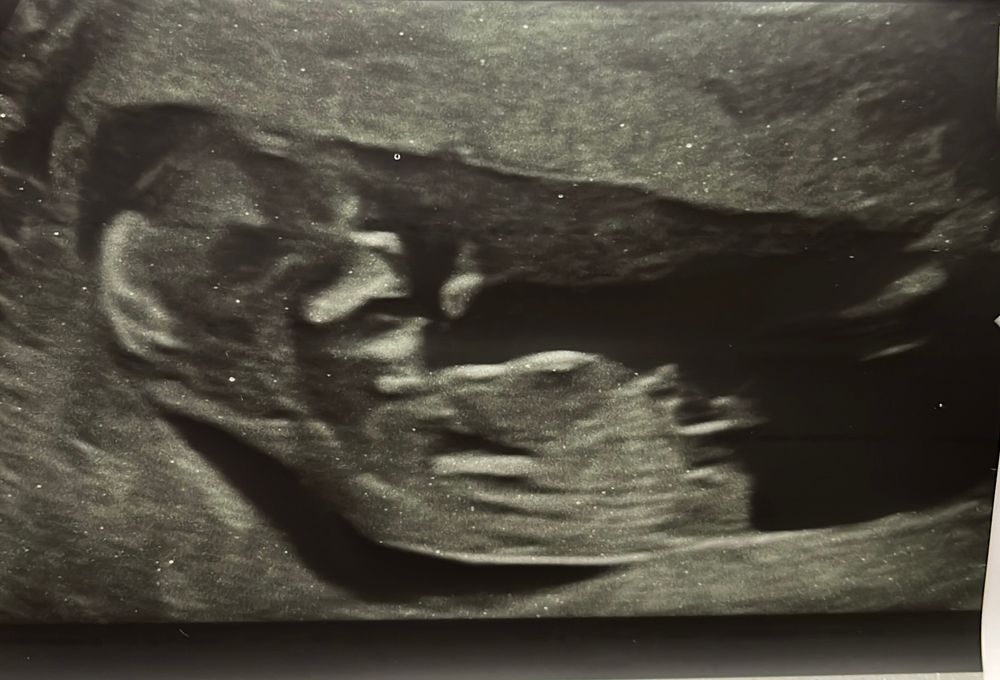

Интересно, где тут бугорок? Если полоска белая, то больше к девочке. Если сверху маленький короткий - это бугорок, то больше к мальчику.

Буду мамой дочки , во такое еще дали) Изображение

Нателла, ну вроде девочка. Но вот эта длинная белая черточка - это точно не бугорок. Под ней короткая - возможно.

Буду мамой дочки , ну здесь ракурс будто сверху и поэтому видно ручки и белая полоса возможно ножка) в общем странные снимки дали)

Нателла, может, это бугорок )) Изображение

Буду мамой дочки , может, ну либо палец от руки🙈